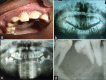

Results and conclusion: This paper is an institutional experience of clinicopathological profile of diagnosed cases of CGCG. Clinicopathological findings were in concurrent with previous literature. Total number of cases was ten. Six occurred in females and four in males. Most of them occurred in the second decade, more commonly involving mandible. Three cases showed recurrence. Histologically most showed classical features. Expression of p63 showed negativity in all the cases in accordance with the previous studies. RANK and RANKL showed strong and diffuse immunoexpression in both mononuclear and giant cells. Thus study supports the finding that p63 expression can be used to differentiate between CGCG and GCT. However, more number of studies with larger sample size are required to confirm reliability of using p63 as a distinguishing marker between GCT and CGCG.